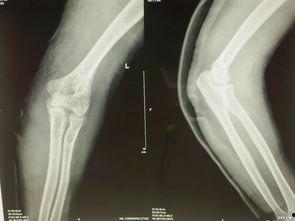

1. 身体伤害:滑车事故可能导致骨折、脑震荡、内脏损伤等严重后果。